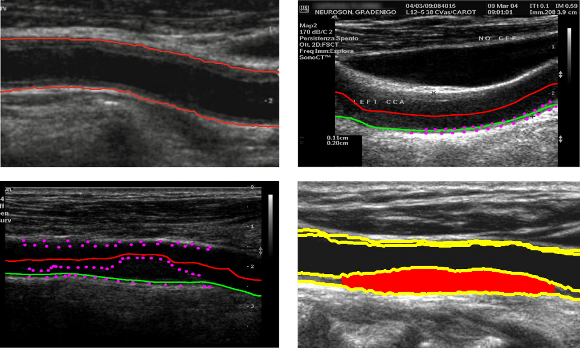

The Carotid CAD project aims at measuring macro vascular markers of atherosclerosis, such as the intima-media thickness (IMT) and plaque burden from carotid US images. The relation of these markers to the presence of cerebral vessel diseases will be studied.

Ultrasonography of the common carotid artery (CCA) has become widely used in clinical practice for the diagnosis of atherosclerosis and associated diseases, as it is a high resolution, noninvasive, low cost and readily available medical imaging technology. From a longitudinal B-mode ultrasound image of the CCA, it is possible to measure the intima-media thickness (IMT), the lumen diameter, or to identify atherosclerotic plaques.

The measurement of macro vascular markers related to the intima-media thickness, the degree of stenosis, the plaque burden or plaque morphology from these ultrasound images of the carotid can be used for early diagnosis of atherosclerosis and stroke risk stratification.

The main objective of the Biomedical Imaging Lab consists of designing and implementing methodologies to automatically obtain these vascular markers and develop CAD tools that help the expert clinicians to early diagnose the patients’ condition.